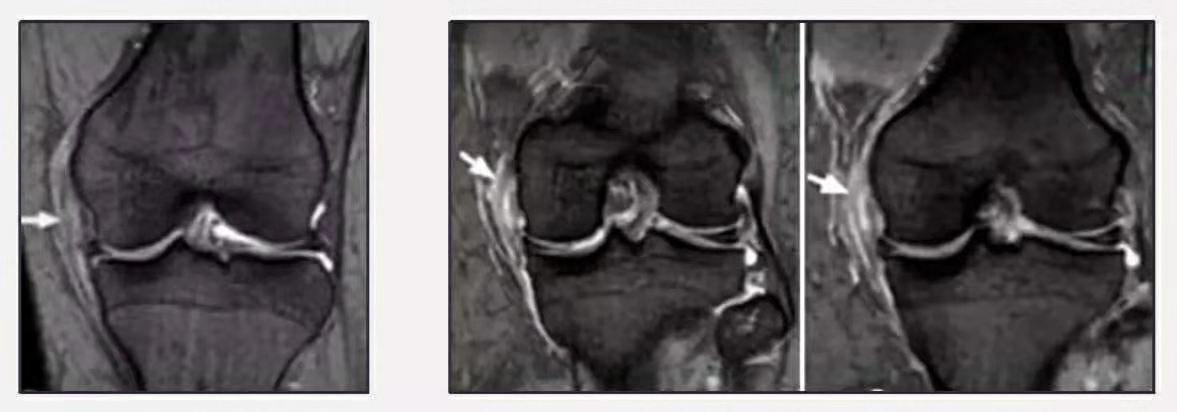

MRI检查是发现内侧副韧带损伤的首选影像学检查方法,并能判断其损伤分级。

II度:韧带内侧(浅层)高信号,伴水肿或韧带部分中断;

图5.内侧副韧带II度损伤(图片来源于网络)

III度:韧带完全断裂。

图6.内侧副韧带III度损伤(图片来源于网络)